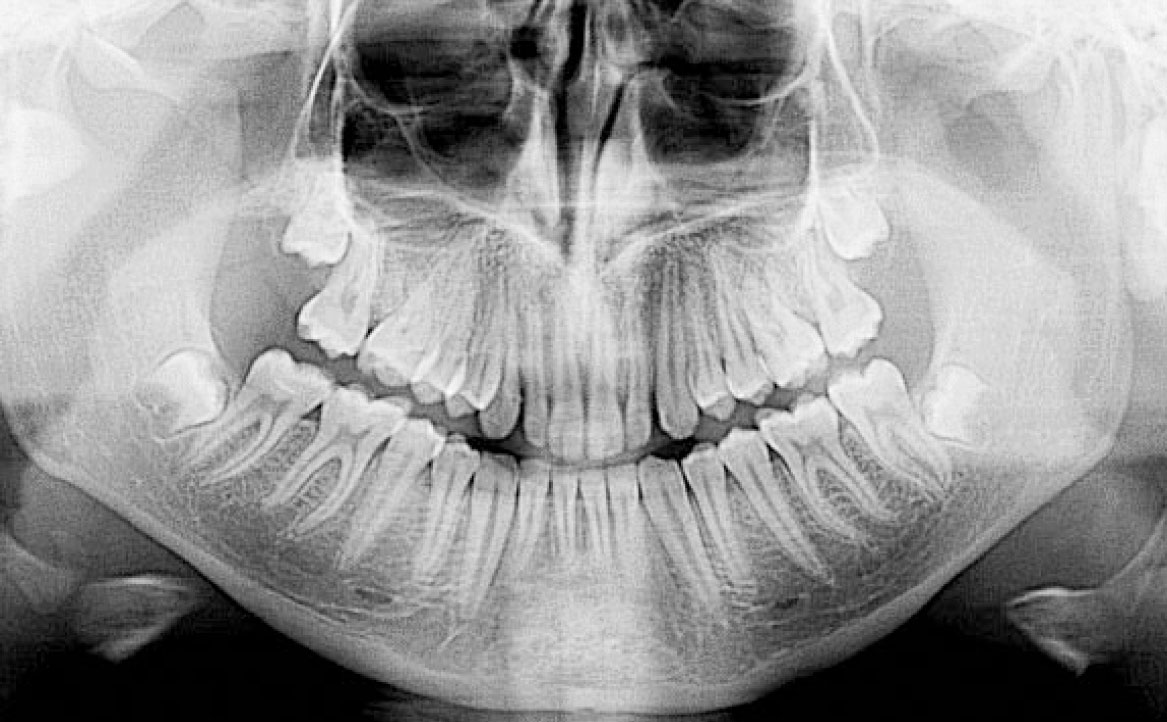

In primo luogo, sono stati prescritti entrambi gli esami radiografici ortodontici: OPT e teleradiografia latero-laterale del cranio (fig. 2a-b). Successivamente, in accordo con il genitore, è stata concordata una terapia ortodontica in due tempi. L’inizio della terapia è stato effettuato con Carriere Motion ed elastici di classe II, con l’obiettivo di migliorare la classe molare (fig. 2c-e).

Il paziente è stato rivalutato circa 12 mesi dopo il debonding di entrambe le arcate con un OPT, al fine di valutare il rapporto tra le radici degli elementi dentali, le arcate dentarie, le ossa dei mascellari, i seni mascellari e la struttura ossea delle articolazioni temporo-mandibolari. Attraverso l’OPT è stato testimoniato che i risultati ottenuti con il trattamento ortodontico erano ancora altamente qualitativi sia dal punto di vista funzionale che estetico a 12 mesi dalla fine del trattamento (fig. 8a) e includevano: una classe I del primo molare e del canino, un allineamento degli elementi superiori e inferiori, una proclinazione degli incisivi superiori, un’apertura del morso e una lieve derotazione dei molari superiori.